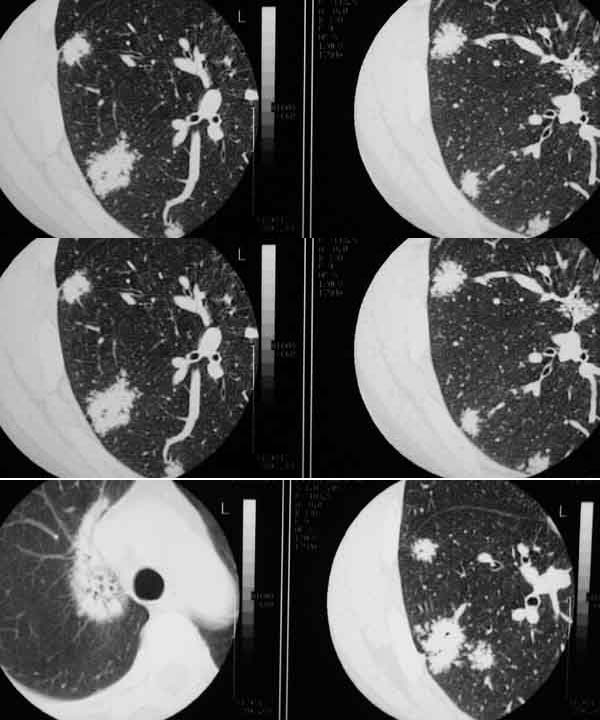

球形肺炎:病变密度相对较淡,中央密度略高,ct图片上密度较为均匀,增强中央可出现无强化区。病变邻近胸膜反应较为显著,可表现为增厚、粘连(可以比较广泛),病变内可以见到大血管的贯穿,周围及近肺门侧可以见到血管纹理增多、增粗,可有支气管充气征象,两侧可垂直于胸膜或呈方形,边缘可为刀切征,它可以出现毛刺样的类似改变,短期内抗炎治疗有效。

ct2533:张巍 提供 患男,24岁,胸痛数月.

穿刺活检为干酪坏死物.胸壁结核瘤!

ct1240:song7715

病人24岁,身体偏瘦,半月前曾有高烧,现无阳性体征,血项不高。透视时无意发现。

右肺结节病理结果:结核球http://www.radida.com/radinet/read.php?tid=3611

ct1585:liuwensi 提供

m,64y,体检发现右肺上叶后段孤立性结节,纵隔内未见肿大淋巴结影右肺病理是结核球

http://www.radida.com/radinet/read.php?tid=4599